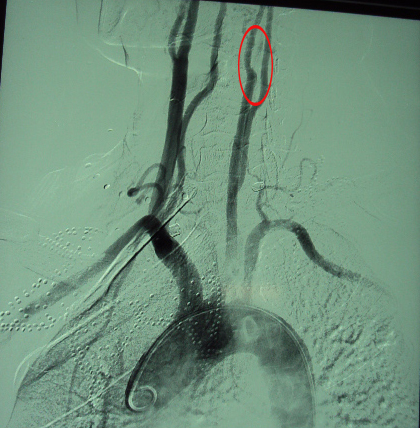

脑血管造影示:右侧颈动脉血流通畅,左侧颈内动脉已经闭塞,但远端虹吸段和左侧大脑中动脉尚有血流通过。

可见侧枝血流通畅

左侧颈内动脉闭塞未显影

经过分析,付某的左侧颈动脉虽已闭塞,但由于前交通支等侧枝的代偿,左侧脑组织并非完全没有了血液供应,即脑细胞并非完全坏死。因此,通过手术取出斑块,通畅左侧颈内动脉血流,将会明显改善患者目前的症状。